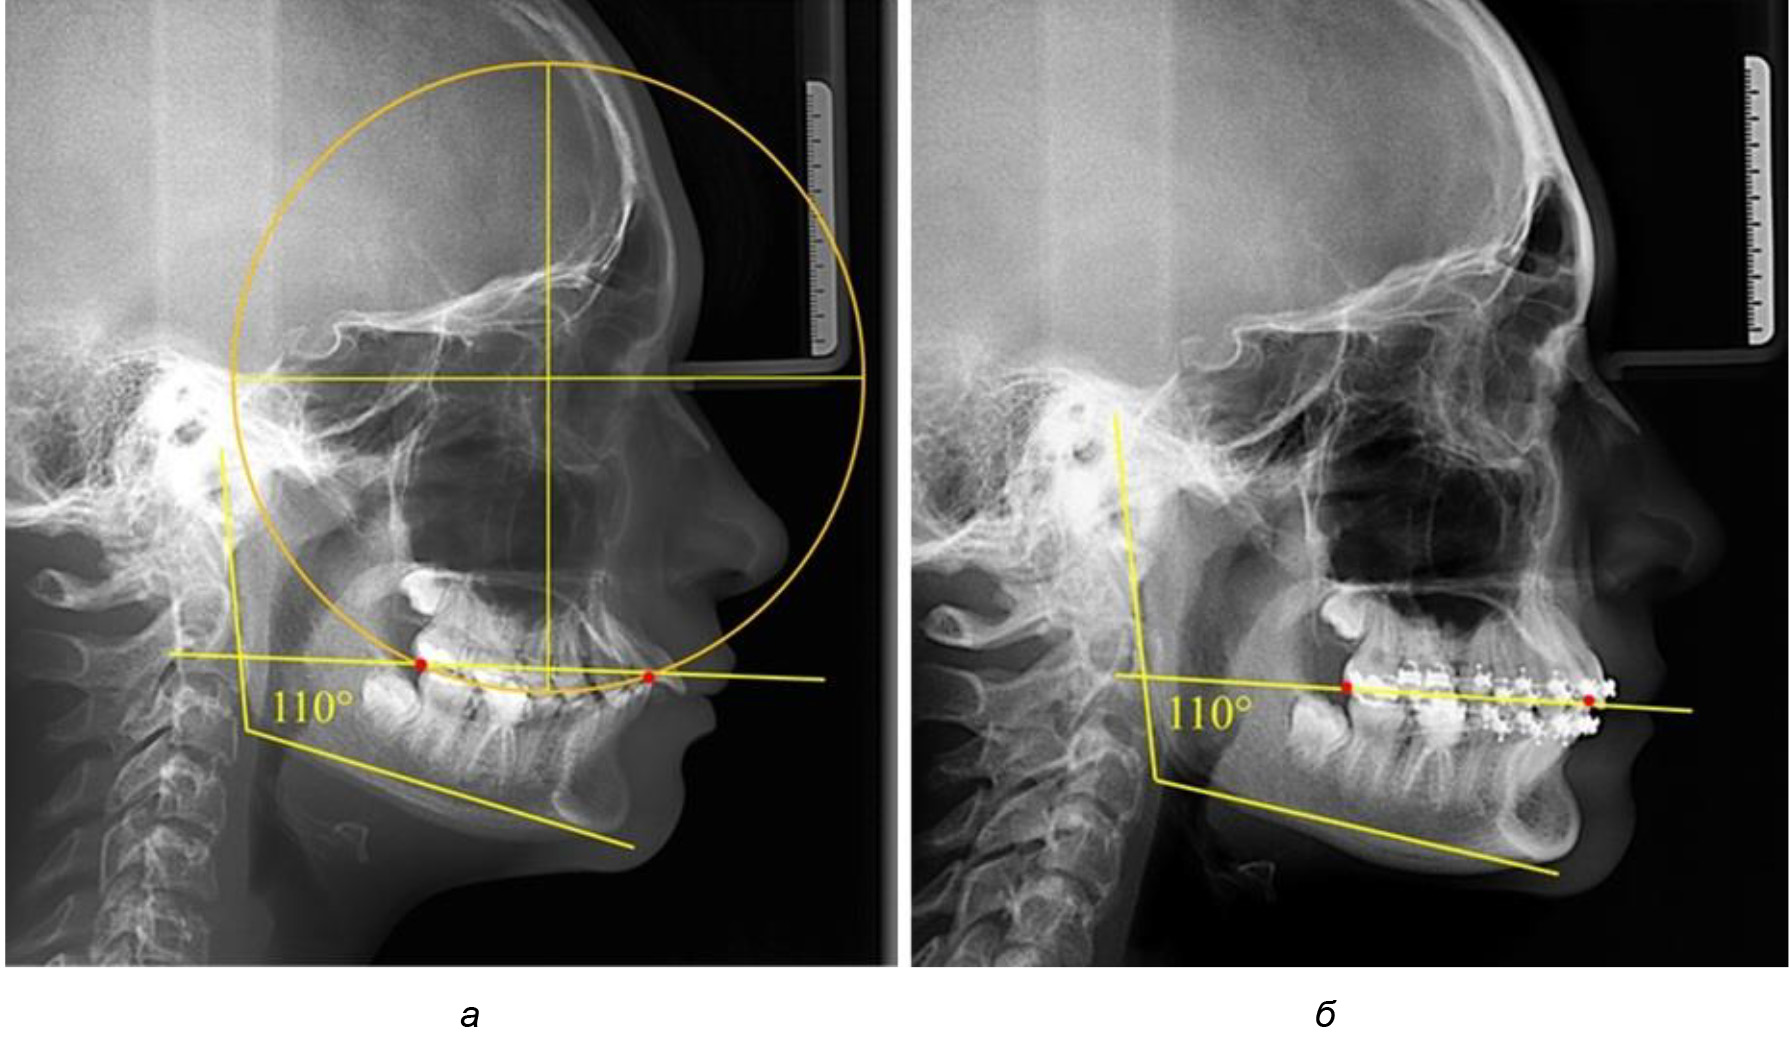

Глубина кривой Spee в среднем по 2-й подгруппе составила (5,69 ± 1,57) мм, что было достоверно больше, чем у людей с физиологической окклюзией (р ˂ 0,05). Достоверных различий с показателями, полученными при анализе ТРГ и ОПТГ, нами не отмечено (р ˃ 0,05). Отношение радиуса окружности к сагиттальному размеру окклюзионной линии в среднем по подгруппе составляло 1,372 ± 0,042 и не соответствовало числу Фибоначчи, что может быть использовано в качестве диагностического критерия определения патологической формы кривой Spee. После лечения пациентов техникой «прямой» дуги было отмечено незначительное увеличение сагиттального размера окклюзионной лини в среднем на (2,12 ± 0,77) мм. Однако окклюзионная линия практически касалась окклюзионного контура всех жевательных зубов, и отмечалось практически полное отсутствие кривой Spee.

Таким образом, проведенное лечение техникой «прямой» дуги способствует нормализации окклюзионного равновесия и торку передних зубов, однако не соответствует оптимальному окклюзионному статусу, характеризующему физиологическую окклюзию. При этом величина нижнечелюстного угла оставалась на прежнем уровне (рис. 5).

Рис. 5. Особенности ТРГ при патологической кривой Spee до лечения (а) и после лечения (б) техникой «прямой» дуги

После лечения пациентов техникой «прямой» дуги, так же как и в 1-й подгруппе, было отмечено увеличение сагиттального размера окклюзионной лини в среднем на (2,38 ± 0,83) мм. Окклюзионная линия практически касалась окклюзионного контура всех жевательных зубов, и отмечалось практически полное отсутствие кривой Spee, так же как и у людей 1-й подгруппы 2-й группы (рис. 6).

Рис. 6. Особенности ТРГ при оптимальной кривой Spee до лечения (а) и после лечения (б) техникой «прямой» дуги

Таким образом, проведенное лечение техникой «прямой» дуги способствует нормализации окклюзионного равновесия и торку передних зубов, однако не соответствует оптимальному окклюзионному статусу, характеризующему физиологическую окклюзию. При этом величина нижнечелюстного угла оставалась на прежнем уровне.